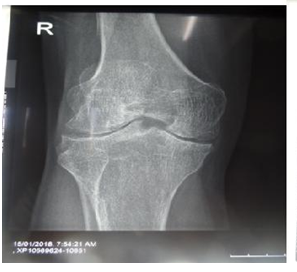

Hemophilia A was dominant in 63.33% of cases and was severe in 90% of cases. More than half of the hemophilia patients involved (n = 19.64%) had hemarthrosis between 3 and 5 times per year. Haemarthrosis was localized most often (n = 12.40%) at the knee level and without any other location (Figure 1). The locations at the elbow (Figure 2) and the ankle (Figure 3 & 4) were less frequent.

Figure 1 Hemarthrosis in the left knee.

Figure 4 Arthropathy in the left knee.

Forty percent of our patients had knee osteoarthritis. Haemarthrosis has been described mainly in the knees according to Nouffissa20 and his collaborators. According to Lobet and colleagues,18 hemarthrosis affects mostly the knees and elbows in subjects over 30 years of age, whereas they mainly affect the ankles in the very young. Diop and colleagues21 reported that hemarthrosis is localized mainly in the knee, then the elbow and ankle. The susceptibility of these joints to hemarthrosis is explained by the fact that they have only one plane of mobility and that any stress outside this plane can lead to a capsulo-synovial elongation source of haemorrhage. In this study, we reported the frequent location of hemarthrosis in the knee. Thus, our data are in good agreement with those of the literature.

70% of patients had knee arthropathy. The study conducted by Windyga10 reported mainly the prevalence of arthropathy in the knee in 92 severe hemophiliacs. In contrast, Strauss and colleagues14 reported 21 cases of hemophiliacs with arthropathy in the elbow. This could be explained by the anatomical complexity of the elbow joint. Utukuri et al.22 also conducted 26 cases of elbow arthropathy in 2005 in London.